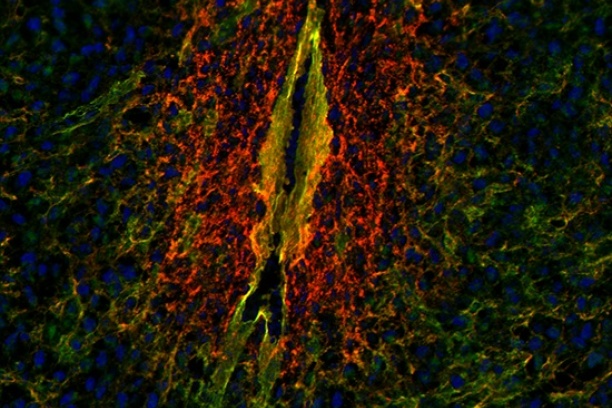

The Digital Histology Shared Resource provides large-scale digital archiving and quantitative analysis of histologic, immunohistochemical and immunofluorescence staining of tissue sections and tissue microarrays. Two Aperio Versa automated scanning microscopes, and Aperio AT2 and a Leica SCN400 Slide Scanner deliver solutions for high-resolution imaging in both bright field and fluorescence. All instruments have high-capacity robotic autoloading (200 slides for the Aperio Versa and Aperio AT2 and 384 slides for the Leica SCN400) making them ideal for large slide cohorts and tissue microarrays. The associated software packages provide complex algorithms for unbiased, automated image analysis and quantitation of immunostaining in both bright field and fluorescence. In addition, these systems can be utilized as a permanent high-resolution solution for those who need archiving of histologic material. The DHSR hosts a convenient, web-based digital slide-viewing environment (Digital Slide Archive) for the rapid retrieval, review, annotation and image acquisition of scanned material. This easy to use digital slide box allows researchers to share images among colleagues from any web browser while remaining in a digitally secure environment. Expert assistance is offered in planning experiments and processing data in a consistent, objective, and timely manner. The automated imaging and analysis performed in this core saves researchers and staff weeks of tedious work. An additional service offered by the DHSR is the creation of digital archives of critical and irreplaceable tissue samples, a benefit only feasible due to the automated high-resolution imaging of whole 25 mm x 75 mm microscope slides and 50 mm x 75 mm "double" slides.